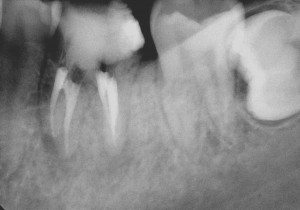

今回の患者様は、もうかれこれ10年の長いお付き合いの患者様です。来院のきっかけは、むし歯の治療でしたが、レントゲン写真から以前の神経を取った治療を行ったところに新たな病気が出来ていました。患者様の希望もあり、根管治療とその後の被せ物の治療も行いました。

約10年前のその当時を思い出してみると、私はマイクロスコープを使った根管治療を始めたばかりの頃だったと思います。いろいろなセミナーに通い、技術を習得していました。

その習得したばかりの技術を用いして何とかこの歯を保存できないかとがんばっていたことと思われます。

現在と比べると、使用している器具や材料では違いはありますが、治療において守るべき基本的なところは変わっておらず、基本に忠実な治療をしたのではないでしょうか。